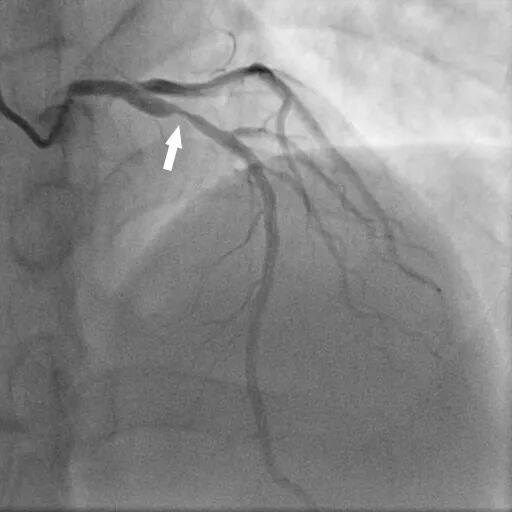

DSA、PCI:

图(6)

图(7)

DSA:前降支(LAD):近段可见85%狭窄,血流TIMI 3级。PCI:于狭窄段置入支架1枚。